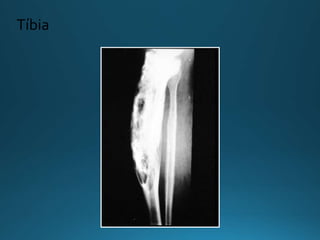

Imagem - Rx

Fase Lítica

Tíbia

• Ossos longos

• Áreas subcondrais de radiotransparência

• Bem delimitada

• Sem esclerose

• ”Folha de grama” ou “Chama deVela” ou “

Cunha progressiva”

• Pode estar isolada à diáfise (tíbia) – Raro

• Ossos longos •Áreas subcondrais de radiotransparência • Bem delimitada • Sem esclerose • ”Folha de grama” ou “Chama deVela” ou “ Cunha progressiva” • Pode estar isolada à diáfise (tíbia) – Raro Imagem - Rx Fase Lítica